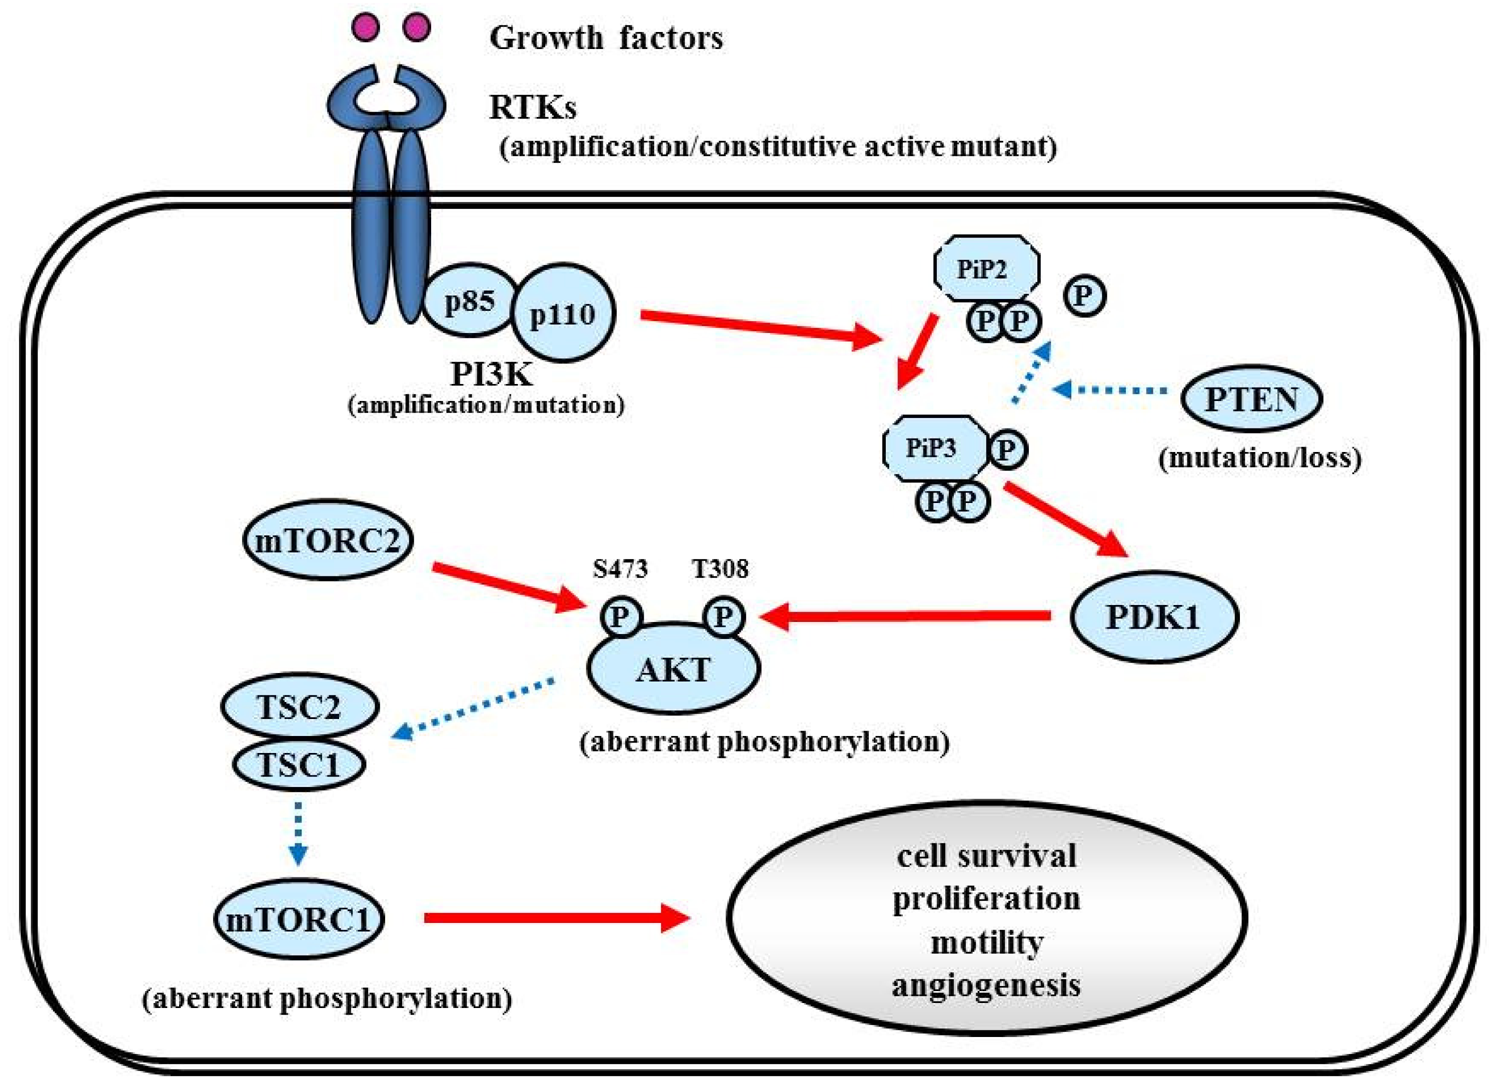

Proliferative activity with histopathologically detectable mitoses is prominent in almost all GBM cases. It is essential to define the contribution of proliferation signaling (or growth factor-mediated signaling) to the GBM cellular phenotype in order to understand the biology of transformation in the CNS. Two of the most important signaling cascades frequently deregulated in glioma are the PI3K/Akt/mTOR and Ras/MEK/MAPK pathways (Figure 3).

The RTK/PI3K/Akt pathway regulates various cellular processes such as proliferation, growth, apoptosis, and cytoskeletal rearrangement. The pathway involves RTKs (EGFR, PDGFR, and VEGFR, etc.) as well as tumor suppressor protein phosphatase PTEN, and protein kinases PI3K, Akt, and mTOR (Figure 6). Aberrant activation of RTK/PI3K/Akt is frequently observed in malignant gliomas because of the alterations of these proteins [81].

7.1.2. PI3K

The PI3Ks are widely expressed lipid kinases that promote diverse biological functions. The binding of PI3Ks and RTKs results in activation of Akt through PiP3 and PDK1, which affects multiple cellular processes including cell survival, proliferation, and motility [98] (Figure 6). The PI3K complex is comprised of a catalytically active protein, p110α, encoded by PIK3CA, and a regulatory protein, p85α, encoded by PIK3R1. Oncogenic mutations or gene amplification of PIK3CA has been reported in various neoplasms including human brain tumors [99]. In primary GBM, PIK3CA mutations and amplification are observed in 5% and 13% of cases [81]. Unlike PIK3CA, PIK3R1 has rarely been reported as mutated in cancers. The TCGA analysis revealed that PIK3R1 mutations were found in 10% (9/91) of GBM cases. According to the integrated genomic classification of GBM, PI3K mutations (15%) are associated with the proneural subtype [1,90]. First generation of the PI3K inhibitors, LY294002 and wortmannin were not applied for clinical trials because of problems in solubility, selectivity, and toxicity [100]. To date, lots of PI3K inhibitors (many of them are PI3K/mTOR dual inhibitors) such as XL147, XL765 (Exelixis and Sanofi-Aventis), BKM120, BEZ235, BGT226 (Novartis), GDC0980 (Genentech), PKI587, PF04691502 (Pfizer), GSK2126458 (Glaxo-Smith-Kline) are currently undergoing Phase I/II trials for GBM patients.

7.1.3. PTEN

Decreased PTEN activity can activate the RTKs/PI3K/Akt pathway since PTEN negatively regulates the pathway by antagonizing PI3K function [101]. Decreased expression of PTEN and activation of Akt have been shown in a variety of cancers, including GBM [102]. Homozygous deletion or mutation of PTEN is a common genetic feature in GBM (∼40%) [1,103,104], resulting in constitutive activation of the RTKs/PI3K/Akt pathway. Some reports implied that GBMs with EGFRvIII and intact PTEN are more likely to respond to EGFR inhibitors [105,106]. PTEN loss is associated with both classical and mesenchymal subtypes of GBM, according to the TCGA study [1].

7.1.4. Akt

Akt is an STK that regulates cell growth, proliferation, and apoptosis. Akt activation has been reported in approximately 80% in human GBMs [46,105], well correlated with the fact that RTKs/PI3K/Akt signaling is altered in 88% of GBM [1]. Oncogenic Akt mutations have not been detected in GBM [107]. Akt inhibitor perifosine is undergoing clinical evaluation in malignant gliomas (NCT00590954) [108].

7.1.5. mTOR

7.5.1. RTKs

RTKs mediate the effects of multiple oncogenic growth factor pathways. Ligand binding to RTK activates PI3K. Activated PI3K activates PDK1 which phosphorylates Akt, which transduces signals for cell survival, proliferation, motility, and angiogenesis as shown in Figure 6. PDGF signaling in neural stem cells is required for oligodendrogenesis, and amplification of this signal induces the aberrant proliferation of neural stem cells and the formation of large glioma-like lesions [162].